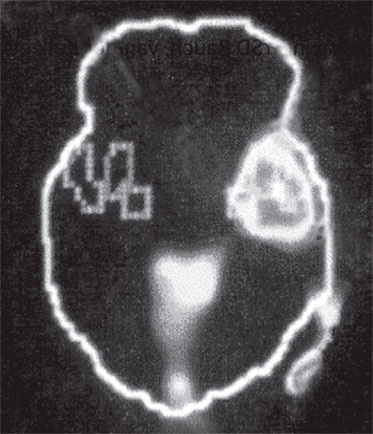

Б. Зрительная кора

Иллюстрация к книге — Тело помнит все [i_003.jpg]

Изображение мозга в процессе переживания травмы. Светлые пятна в лимбической коре (А) и зрительной коре (Б) соответствуют повышенной активности мозга в этих участках. На снимке (В) видна значительно пониженная активность речевого центра мозга.